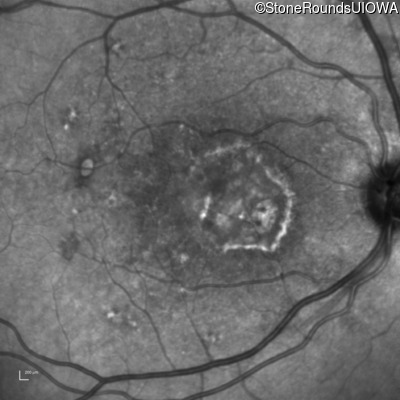

Fluorescein Angiography - Left - 20/20

Exemplar